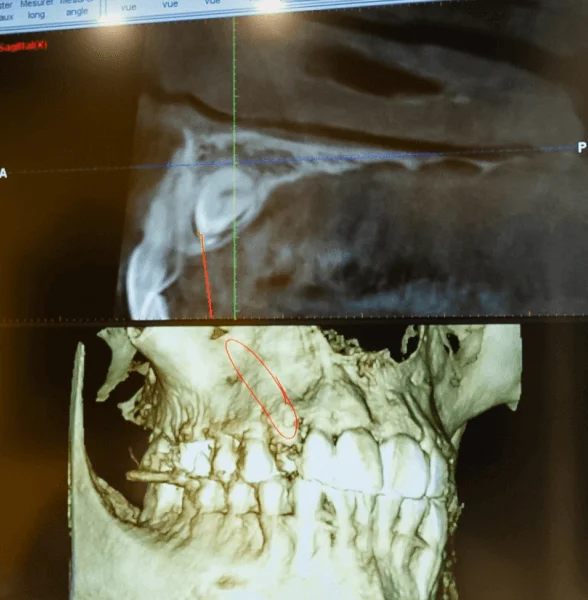

• Examens complémentaires (photographies, radiographies, empreintes numériques).

• Permet au praticien d’établir un diagnostic précis pour proposer un traitement adapté.